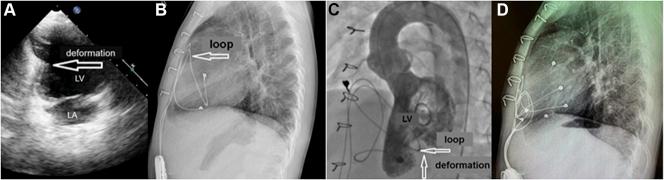

Cardiac strangulation is a rare but potentially life-threatening mechanical complication associated with epicardial pacemaker implantation in growing children. This article presents 2 case reports of left ventricular strangulation in 4- and 3-year-old children who had an epicardial pacemaker system implanted at an early age. ().

心脏绞窄是一种罕见但可能危及生命的机械性并发症,与成长中儿童的心外膜起搏器植入有关。本文报告了2例分别为4岁和3岁儿童发生左心室绞窄的病例,这两名儿童在幼年时植入了心外膜起搏器系统。()